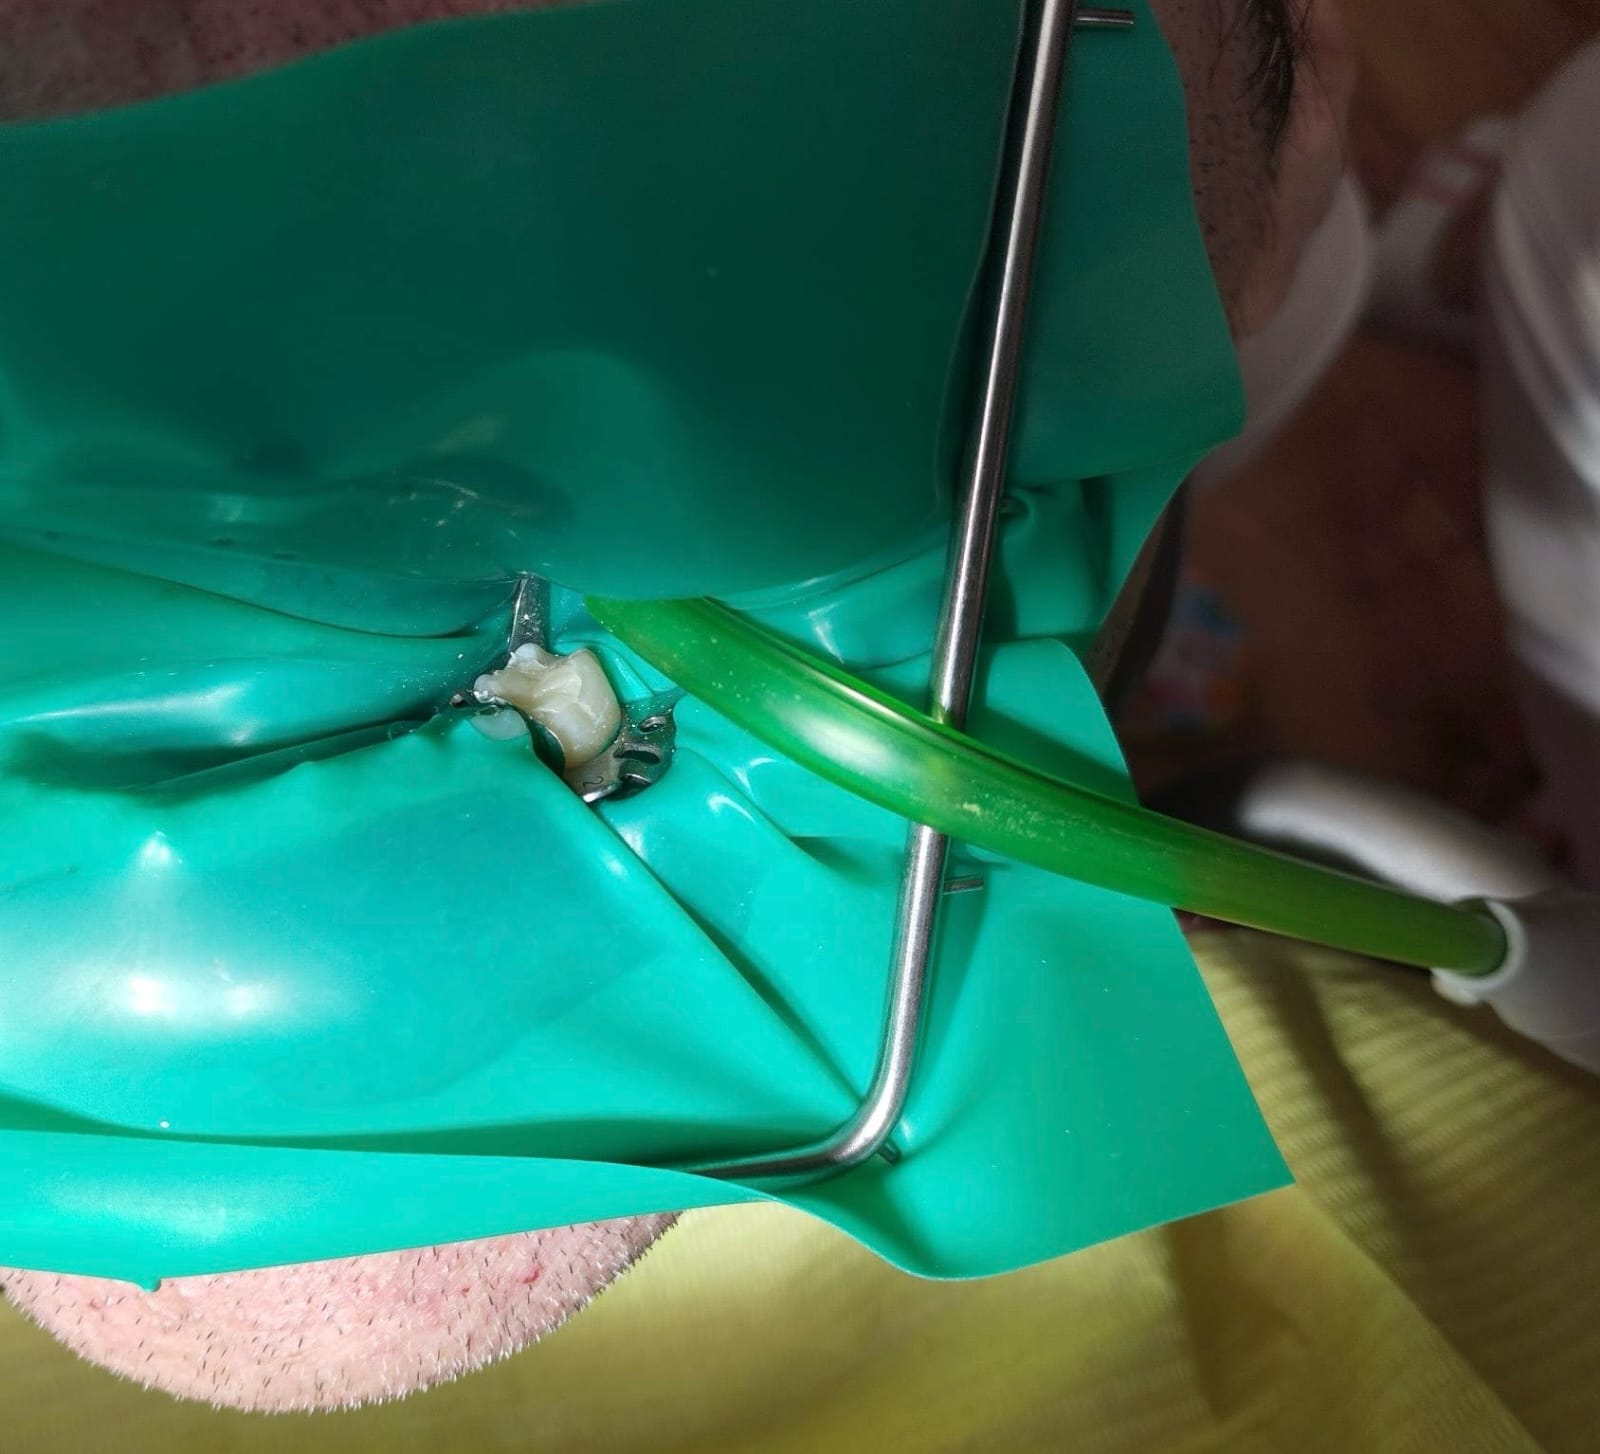

Při zhotovení bílé výplně (fotokompozitní s vysokým obsahem plnidel) dbáme na preciznost a pro udržení suchého pole používáme koferdam. Jeho nasazení je rychlé a použití bezbolestné.